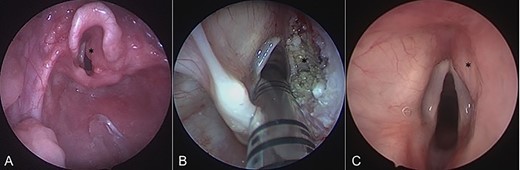

On admission, his oxygen saturations, serum haematology and biochemistry were normal. There was no daytime respiratory distress. At night, he had audible inspiratory stridor, a raised respiratory rate, tracheal tug and apnoeas. He underwent a diagnostic microlaryngoscopy, which showed a large, submucosal, nodular tumour involving the right aryepiglottic fold, false cord, ventricle and the medial wall of the piriform fossa (Fig. 2A). Histological analysis of biopsies described multiple tortuous nerve fascicles; the clinical suspicion of a plexiform neurofibroma was confirmed.

Intraoperative endoscopic images of the supraglottis: (A) before intervention; (B) after debridement; and (C) at 16 months after surgical intervention. Asterisk denotes area of interest.

The case was discussed in the Head and Neck multi-disciplinary team (MDT) meeting. Due to the patient’s age, co-morbidities and the site of the lesion, the MDT felt that complete surgical excision—requiring resection of the right aryepiglottic fold, false cord and ventricle—would result in significant morbidity. The child would be at risk of aspiration, dysphagia, dysphonia and laryngeal scarring. Therefore, we opted to use a coblation technique to debulk the neurofibroma (Fig. 2B).

Post-operatively, the number of observed apnoeic episodes improved significantly. However, intermittent noisy breathing at night was ongoing, so, 3 months later, the patient underwent a further debridement, as well as coblation intracapsular tonsillotomy and adenoidectomy. Following this, his symptoms improved considerably, with noisy night-time breathing resolving, and serial sleep studies showing significant improvement. He did not experience any dysphagia or aspirations, confirmed by a review from a speech and language therapist.

Sixteen months after the second debridement, the patient had a largely asymptomatic airway, stable disease on MRI scans (Fig. 1B) and no signs of significant lesional growth or airway obstruction on repeat microlaryngoscopy (Fig. 2C). At 30 months follow-up, imaging shows the neurofibroma to have mildly increased in size but there are no significant respiratory symptoms and no functional impairment.